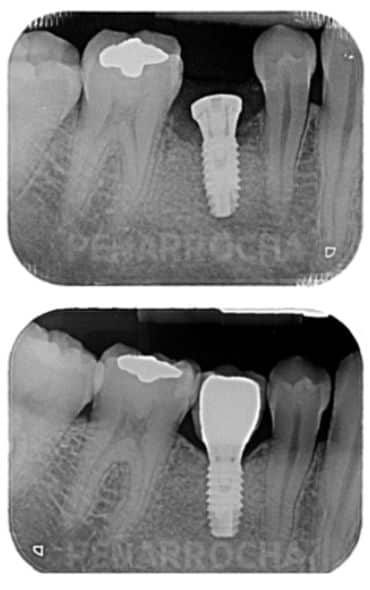

Una de las posibles razones podría ser una periimplantitis periapical, un trastorno infeccioso-inflamatorio que afecta al extremo del implante dental y que puede desarrollarse durante el proceso de osteointegración. No obstante, no hay motivo de alarma: este problema suele tratarse eficazmente mediante una limpieza quirúrgica del área afectada y, en la mayoría de los casos, presenta un buen pronóstico.

Los síntomas y plazos que comentas son característicos de una patología relacionada con los implantes que se conoce como «patología periapical al implante» o «peri-implantitis temprana». Suele ocurrir en aproximadamente el 0,5% de los implantes, y es más frecuente cuando el implante sustituye a un diente que fue tratado con endodoncia o cuando alguno de los dientes vecinos tienen una endodoncia.

También sirve para que, si volviera a pasarte, no asumas como normal el dolor de esos primeros días, y acudas a la clínica dental. La «patología periapical al implante» tiene solución si se trata correctamente y de forma precoz; en un 80-90% de los casos conseguimos salvar los implantes con una sencilla intervención. Y la forma de detectarla es precisamente el dolor agudo durante las primeras semanas: los implantes dentales no duelen, más allá de una ligera molestia postoperatoria que dura unos días y se puede sobrellevar perfectamente con ibuprofeno o paracetamol. Si duelen mucho, es que algo va mal y hay que acudir a la clínica dental a descartar problemas.

Existe una complicación relativamente infrecuente de los implantes dentales que cursa con dolor moderado-severo tras varias semanas de la cirugía de implantes. Se llama periimplantitis temprana, periimplantitis apical o patologia periapical al implante. En el 90% de los casos tiene solución con un sencillo tratamiento quirúrgico, y si no se trata suele desembocar en el fracaso del implante afectado. La clave es diagnosticar si la causa de tu dolor puede ser este problema, para poder solucionarlo.